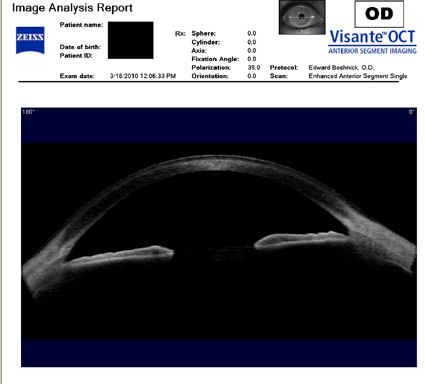

Следующие изображения были получены с использованием метода, называемого оптической когерентной томографией, или ОКТ. Прибор позволяет получить изображение в поперечном сечении путем сканирования передней части глаза (переднего сегмента) лучом света. Думайте об этом как об ультразвуке, использующем свет вместо звуковых волн для создания изображения живых тканей.

На изображении, приведенном непосредственно ниже, представлен снимок здоровой, неоперированной роговицы для сравнения со следующими изображениями эктатических роговиц после операции LASIK.

На снимке ниже показана эктазия роговицы после операции LASIK. Толщина роговицы в самом тонком месте составляет всего 250 микрон, что в два раза меньше толщины нормальной роговицы. Пациент носит большие терапевтические контактные линзы. Белая изогнутая линия вверху обозначает переднюю поверхность хрусталика. Ниже расположена более слабая белая изогнутая линия, обозначающая заднюю поверхность хрусталика. Между хрусталиком и роговицей находится пространство, заполненное физиологическим раствором, который имеет зернистый вид. Нажмите на изображение, чтобы увеличить его.

На изображении ниже представлен снимок роговицы в поперечном сечении после операции LASIK. Белая изогнутая линия вверху - это передняя поверхность твердой контактной линзы. Следующая едва заметная белая линия - это задняя поверхность линзы. Следующая область, которая имеет зернистый вид, - это пространство между хрусталиком и роговицей, заполненное физиологическим раствором. Роговица имеет классические признаки эктазии - истончение, выпуклость и неправильную форму.

Изображения любезно предоставлены доктором Эдвардом Бошником, который посвятил свою практику восстановлению качественного зрения и информации о эктазия после операции LASIK .